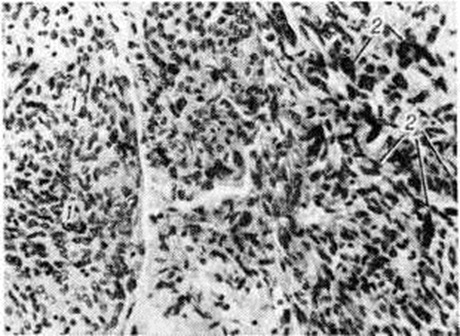

МенингиомаМенингиома (meningioma, греческий meninx, meningos мозговая оболочка + -oma; синонимы: грибовидная опухоль твёрдой мозговой оболочки, фиброэндотелиома, менинготелиома, арахноидэндотелиома, арахноидальная менингиома, менингеальная фибробластома, менингобластома) — внемозговая, в большинстве случаев доброкачественная опухоль, исходящая из твёрдой, реже мягкой оболочки головного или спинного мозга, редко из сосудистого сплетения мозговых желудочков или возникающая эктопически в костях черепа, позвоночника и по ходу нервных корешков. По локализации различают: 1. Менингиома оболочек головного мозга: 1) конвекситальную; 2) парасагиттальную — встречается вдоль угла, образованного стенкой верхнего продольного синуса и твёрдой мозговой оболочкой выпуклой поверхности больших полушарий; может сдавливать синус или врастать в него; 3) большого серповидного отростка; 4) тенториальную; 5) твёрдой мозговой оболочки основания мозга: а) передней черепной ямки — ольфакторной ямки, бугорка турецкого седла; б) средней черепной ямки — крыльев основной кости; в) задней черепной ямки — блюменбахова ската, края большого затылочного отверстия. 2. Менингиома оболочек спинного мозга. 3. Внутрижелудочковую Менингиома, исходящую из сосудистого сплетения. 4. Экстрадуральную Менингиома — исходит из наружных слоёв твёрдой мозговой оболочки, часто инфильтрирует прилежащие кости черепа, стенки позвоночного канала. Менингиома, связанные с оболочками зрительного нерва, располагаются в зрительном канале, в полости орбиты. 5. Эктопическую Менингиома—встречается в костях черепа и позвоночника, в придаточных полостях носа, в полостях внутреннего и среднего уха, по ходу нервных корешков. Микроскопически Менингиома обычно представляет собой хорошо отграниченный узел округлой или полдовоидной формы (рисунок 1), нередко спаянный с внутренней поверхностью твёрдой мозговой оболочки. Встречаются и плоские узлы. Спинальная Менингиома чаще продолговатая, при экстрадуральном расположении может муфтой охватывать дуральный мешок. По величине Менингиома варьируют в диаметре от нескольких миллиметров до 15 сантиметров и более. Консистенция Менингиома довольно плотная, особенно при обилии фиброзной ткани. В большинстве случаев опухоль окружена плотной капсулой. На разрезе ткань Менингиома серо или мясо-красная, при обильном содержании так называемый ксантомных клеток принимает охряную окраску. Наличие кист в Менингиома не характерно. Менингиома обычно одиночны, но могут быть и множественные. В редких случаях множественная Менингиома сочетается с множественной невриномой — болезнь Реклингхаузена (смотри полный свод знаний Нейрофиброматоз). Гистологический классификации Менингиома не отличаются существенно одна от другой. Согласно гистологической классификации опухолей центральная нервная система, принятой Комиссией ВОЗ по опухолям мозга (Женева, 1976), выделяются следующие подтипы Менингиома: Менинготелиоматозная Менингиома (эндотелиоматозная, синцитиальная, арахноидэндотелиоматозная). Состоит из мозаикоподобно-расположенных мономорфных клеток с овальным или округлым ядром, содержащим умеренное количество нежных зёрен хроматина. Строма представлена немногочисленными сосудами и редкими тонкими тяжами соединительной ткани, окаймляющими клеточные поля. Характерны, но не всегда встречаются концентрические структуры, подобные разрезанной луковице, из наслаивающихся одна на другую уплощённых опухолевых клеток. Гиалинизированный центр такой структуры нередко обызвествляется (так называемый псаммомное тельце). Фиброзная Менингиома (Фибробластическая). Построена из фибробластоподобных клеток, которые располагаются параллельно друг другу и складываются в переплетающиеся между собой пучки, содержащие соединительнотканные волокна (рисунок 2). Ядра клеток вытянутые. Могут встретиться концентрические структуры, псаммомные тельца. Переходная Менингиома (смешанная). Включает структуры менинготелиоматозной и фиброзной Менингиома Псаммоматозная Менингиома — менинготелиоматозная или фиброзная Менингиома с большим количеством псаммомных телец. |

Рис. 1. | ||